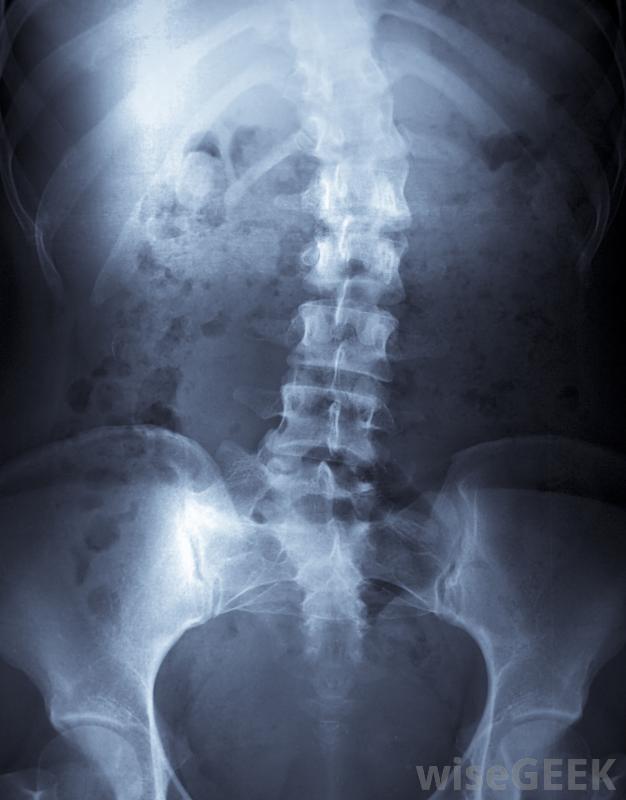

密尔沃基支撑架用于矫正背部中部的曲线,也被称为高胸椎。

密尔沃基支架可用于减缓脊柱侧凸的进展。